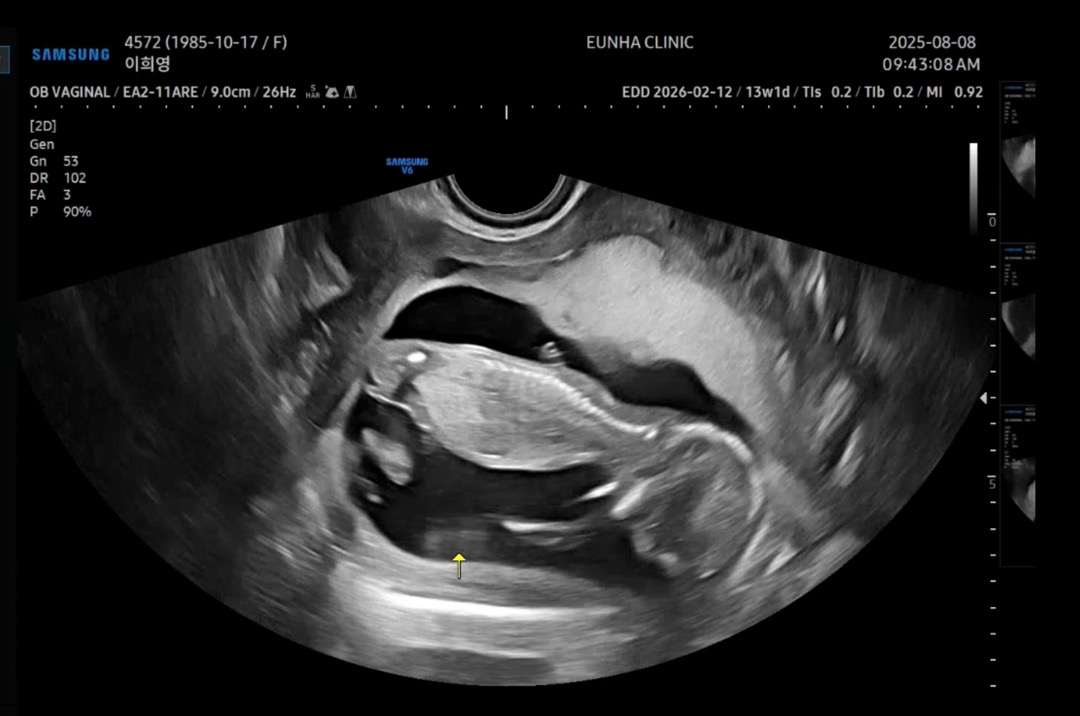

13주차 각도법

이 사진으로 문의드리는게 맞는지도 모르겠네요 ㅎㅎ 의사샘도 촘파 열심히 봐주시더니 애매하다고 아직은 모르겠다고 하셔서 더 애가 타요ㅠㅠ

뒤집어보면 보여요. 딸각도 같아요.

저게 생식기가 맞다면 딸 각도 맞겠죠? ㅎㅎ 감사합니다😍